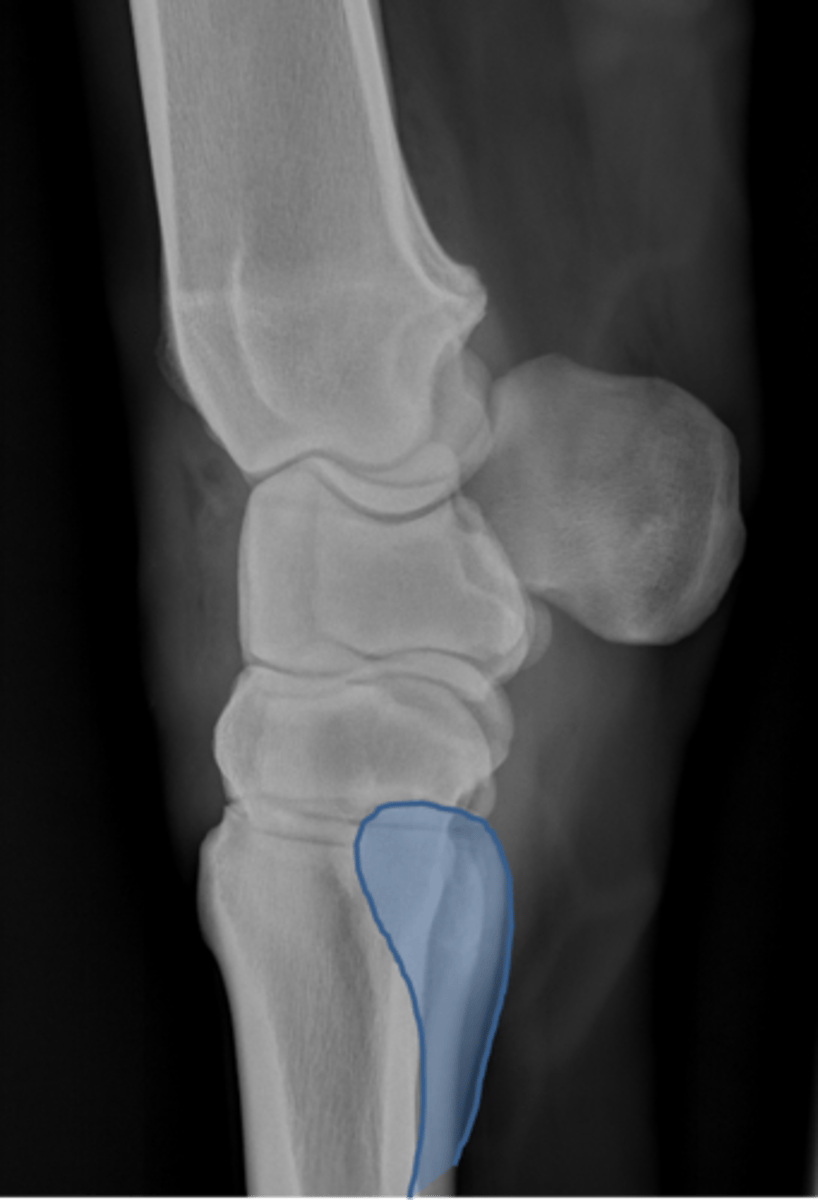

Carpus, lateral

ID joint and view

Antebrachiocarpal joint

Middle carpal joint

Carpometacarpal joint

Radial carpal bone

Intermediate carpal bone

Ulnar carpal bone

Third carpal bone

Second carpal bone

Fourth carpal bone

Accessory carpal bone

Second metacarpal (medial splint)

Fourth metacarpal (lateral splint)

Cannon bone